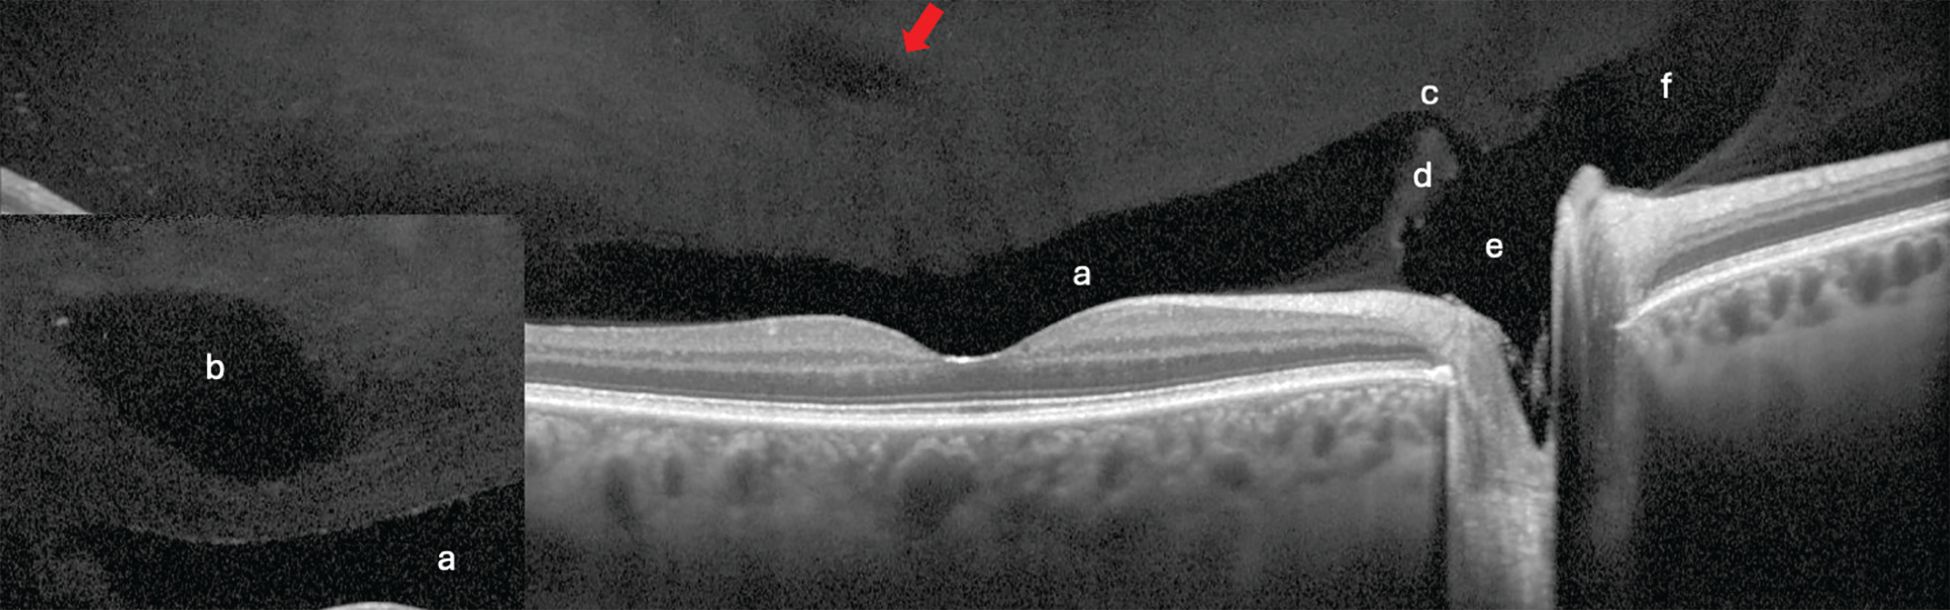

Figure 3. Vitreoschisis may occur anteriorly to the hyalocytes, which results in a more equal-appearing thickness of the separation (Figures 3a and 3c). Image courtesy of Jim Williamson, OD, FAAO, FORS.

Figure 3. When the vitreoschisis occurs posterior to the hyalocytes, a thinner membrane remains (Figure 3b). Image courtesy of Jim Williamson, OD, FAAO, FORS.

Figure 3. Vitreoschisis may occur anteriorly to the hyalocytes, which results in a more equal-appearing thickness of the separation (Figures 3a and 3c). A break in the posterior vitreous cortex appears in Figure 3c (arrow). Image courtesy of Jim Williamson, OD, FAAO, FORS.

Sometimes during an anomalous PVD, a vitreoschisis may occur where the posterior vitreous cortex splits, which leaves the cortex’s outermost layer still attached to the retina. On optical coherence tomography (OCT), this appears as 2 layers joining into 1, forming a lambda (l) or Y sign (Figure 3).12 The posterior vitreous cortex contains hyalocytes, and when the split occurs posterior to them, a thin membrane remains. If the break occurs anteriorly, the hyalocytes stay put. Researchers suggest a role with the former in macular holes and the latter with macular pucker and tangential vitreoretinal contraction.12